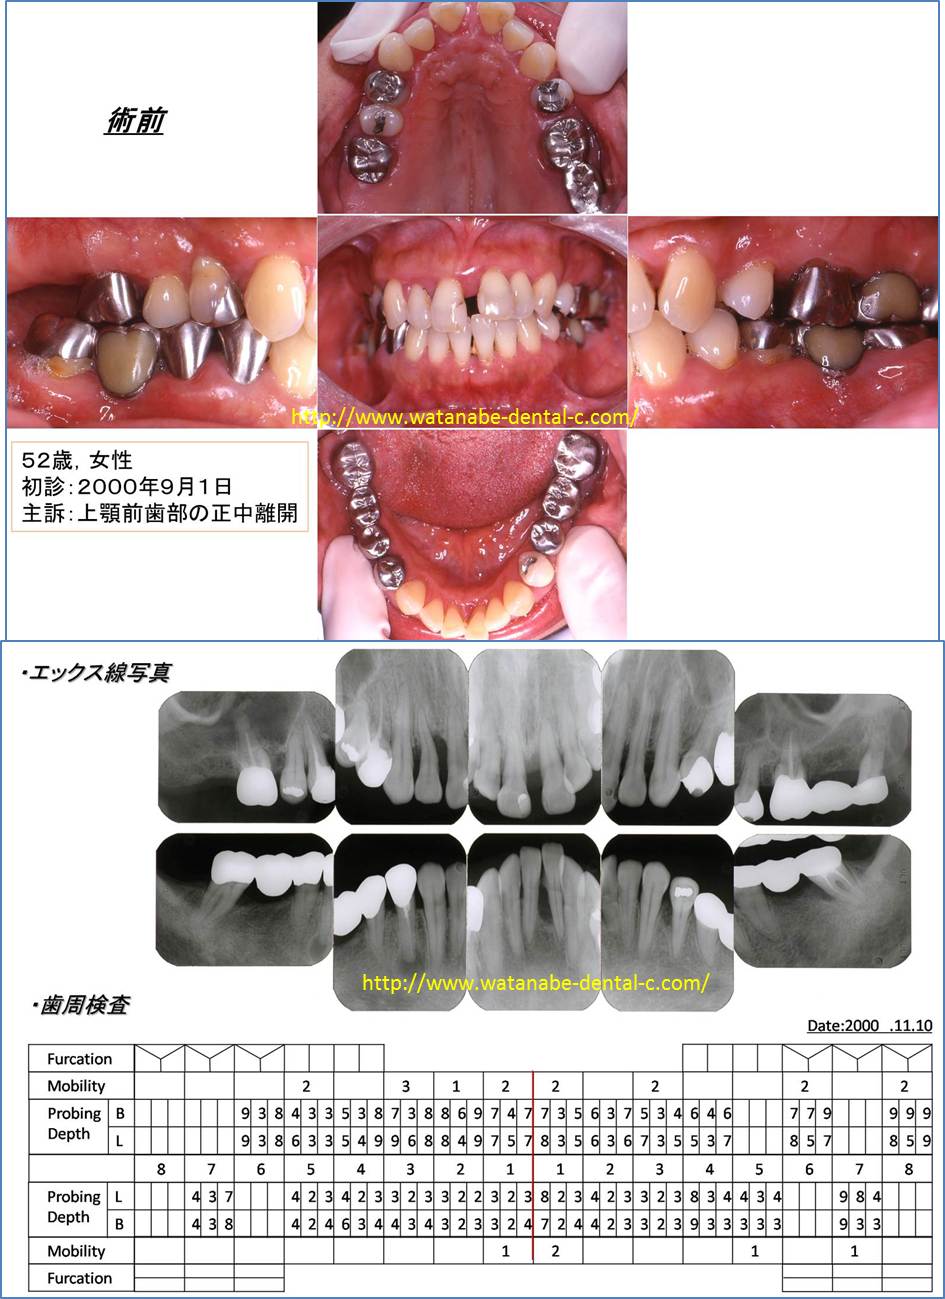

2.歯周病症例(主訴:前歯の開きが気になる。)

52歳女性、上の前歯が開いていることが気になり来院されました。前歯の間が開き、歯肉が腫れています。エックス線撮影、歯周ポケットの検査を行っています。全体的に5mm以上の歯周ポケットが認められます。このような場合、開いてしまった歯を削って冠を被せてしまえば、解決するのでしょうか?それでは解決しません。見た目の問題を解決しても、歯肉の中の根が汚染されていれば、冠を被せて一時的に見た目が回復しても、また開いてきてしまいます。そこで「治療計画」を立案します。ホームページでも示したように歯周病治療に限らず、歯科治療は「治療計画」がとても重要になります。その治療計画は「歯周病治療」をベースとしたものでなければならないと私は考えています。

まずは、歯周基本治療である炎症性因子のコントロールを行います。患者さんに1.歯間ブラシ、2.歯ブラシ、3.ワンタフトブラシにてブラッシング指導、スケーリング(歯石をとること)、スケーリング・ルートプレーニング(歯肉の中の根に付いている歯石をとり、汚染した根をきれいにすること)、不良な被せものを外して仮の歯の製作、左上の一番奥の歯は保存できないため抜歯。その後、再評価をします。歯周病治療では、この「再評価」がとても重要になります。「再評価」は、再度、歯周ポケット検査、歯の動揺、噛み合わせの確認を行います。この時点で歯周ポケットが改善されれば、歯周病治療は経過をみながら、被せものの治療へと移行します。しかしながら、特に奥歯に関しては歯周基本治療だけでは歯周ポケットは改善しにくいのです。「歯周基本治療」は「原因除去療法」といいます。歯の表面のプラークの除去、歯肉の中の歯肉縁下歯石の除去、無理な噛み合わせの調整により歯周病の原因および悪化させている原因を除去します。これで治れば一番良いのですが、まだ歯周ポケットが残っている場合は、「歯周外科処置」へ移行するのが望ましいです。この症例の場合、奥歯に関しましては歯肉剥離掻爬術を施行しました。